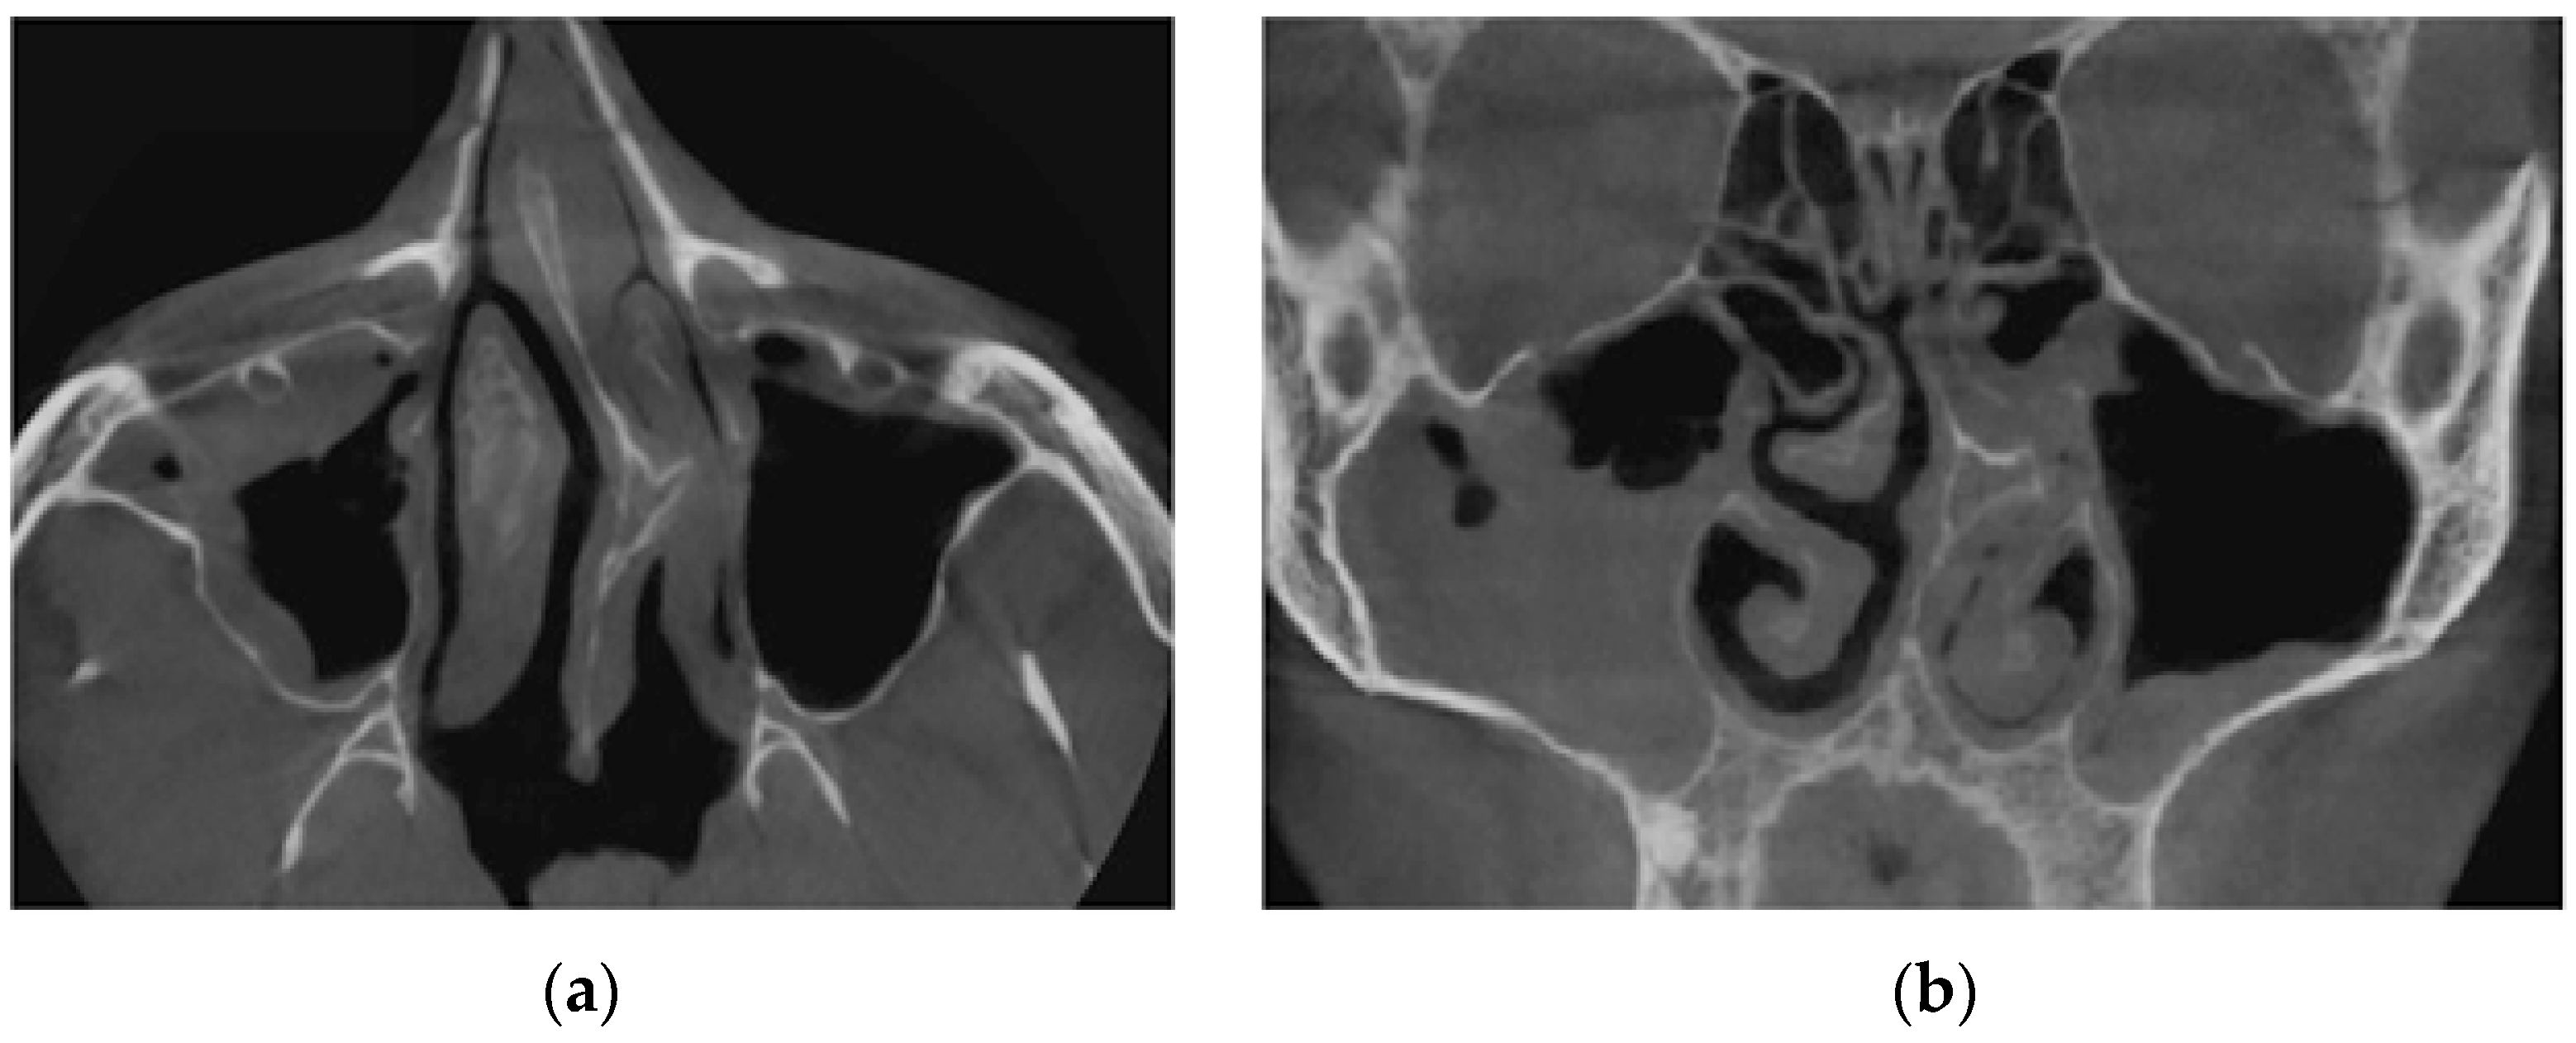

Figure 14 provides a visualization of the local curvature of the nasal septum to the left in the posterior part of the nasal cavity, which is displayed on the axial—see Figure 14, and the frontal—Figure 14b tomographic sections.

Figure 15 shows the thickening of the nasal mucosa in chronic rhinosinusitis, which leads to narrowing of the airways (see Figure 15a,b).